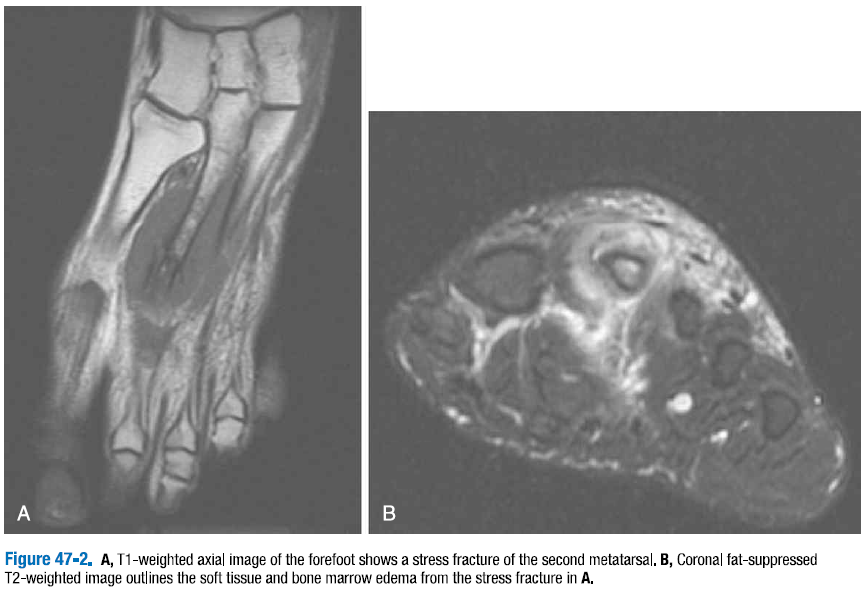

종골과 중족골 피로 골절이 발에 있어서 가장 흔한 피로 골절(stress fracutres)의 부위에 해당한다. T1 강조 영상에서는 골절의 부종과 혈종이 정상적인 높은 신호의 골수를 가로지르는 낮은 신호의 띠 형태로 나타난다. 지방 억제 T2 강조 또는 STIR 영상은 골절 부위의 증가된 신호 강도를 보여준다. (그림 47-2)

△ 그림 47-2. A. 전족부의 T1 강조 축면 영상이 두번째 중족골의 피로골절을 보여준다.

B. 관상면 지방 억제 T2 강조 영상은 연부조직과 피로골절로 인한 골수종의 윤곽을 보여준다.